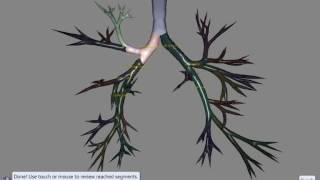

EndoSim Bronchoscopy: Interventional EndoSim Bronchoscopy: Navigation

EndoSim Bronchoscopy: Navigation EndoSim Bronchoscopy: Orientation

EndoSim Bronchoscopy: Interventional EndoSim Bronchoscopy: Navigation

EndoSim Bronchoscopy: Navigation EndoSim Bronchoscopy: Orientation